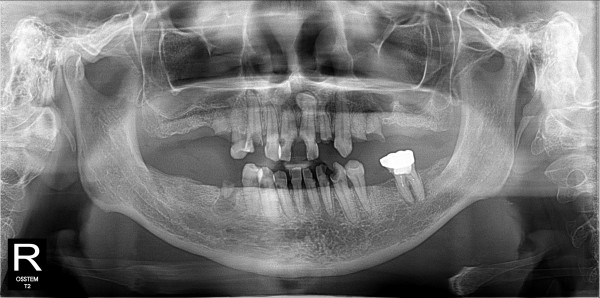

구치부 임플란트 최고관리자 0건 23-11-07 18:32 본문 구치부 임플란트 + 전치부 크라운 목록 이전글네비게이션 임플란트 23.11.07 다음글구치부 임플란트 23.11.07 댓글목록 0 댓글목록 등록된 댓글이 없습니다.